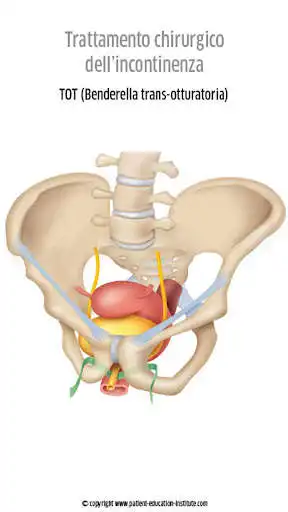

Lapp Patient Education Institute, contenente migliaia di illustrazioni mediche, costituisce un supporto visivo senza eguali che consentir agli operatori sanitari di migliorare la qualit delle conversazioni con i propri pazienti. Ogni situazione clinica si presenta in modo ben strutturato, con illustrazioni, icone e brevi testi esplicativi di facile comprensione.

La situazione di stress in cui si trovano i pazienti durante il consulto li induce a recepire le informazioni in maniera molto ridotta. Proprio per questo motivo i nostri contenuti si distinguono per la semplicit con cui ogni situazione clinica viene presentata, con numerose illustrazioni di alta qualit e di facile comprensione che supporteranno adeguatamente le tue spiegazioni ed eviteranno il profilarsi di complicazioni non necessarie.